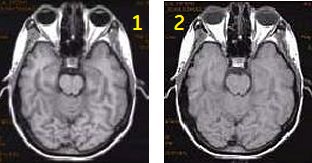

Figure 5. T1FLAIR with ASSET on and off.

Table 3. Image legend

NumberDescription

1ASSET Imaging Option turned on.

2ASSET Imaging Option turned off.